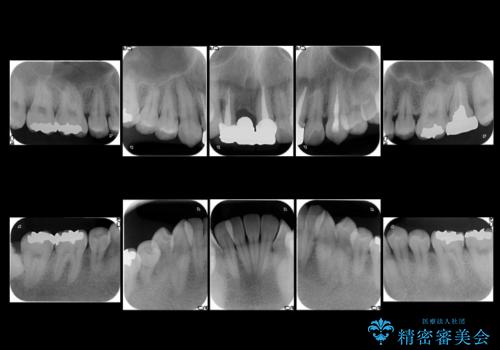

- 前歯のブリッジのやりかえおよび銀の詰め物をセラミックにしたいと来院。

過去に事故で前歯を折って、ブリッジにしたとのことでしたが、支台となる歯が持たない状況で、ブリッジを延長せざるを得ない状況でした。

長いブリッジへ設計変更になるため、下の前歯のがたつきが気になるのであれば、先に矯正治療をしてから最終的なブリッジを入れることをご提案し、全て行なっていくことになりました。

上の前歯の本数が少ないことから、小臼歯を4本抜歯するのではなく下の前歯を1本だけ減らして並べました。

左上1番は再根管治療を行いましたが途中で破折が確認されたため、抜歯しています。

また、大臼歯の銀歯もセラミックに全てやりかえています。

左上7番は歯周病によりやむなく抜歯となり、インプラントをおすすめしましたが、希望されませんでした。